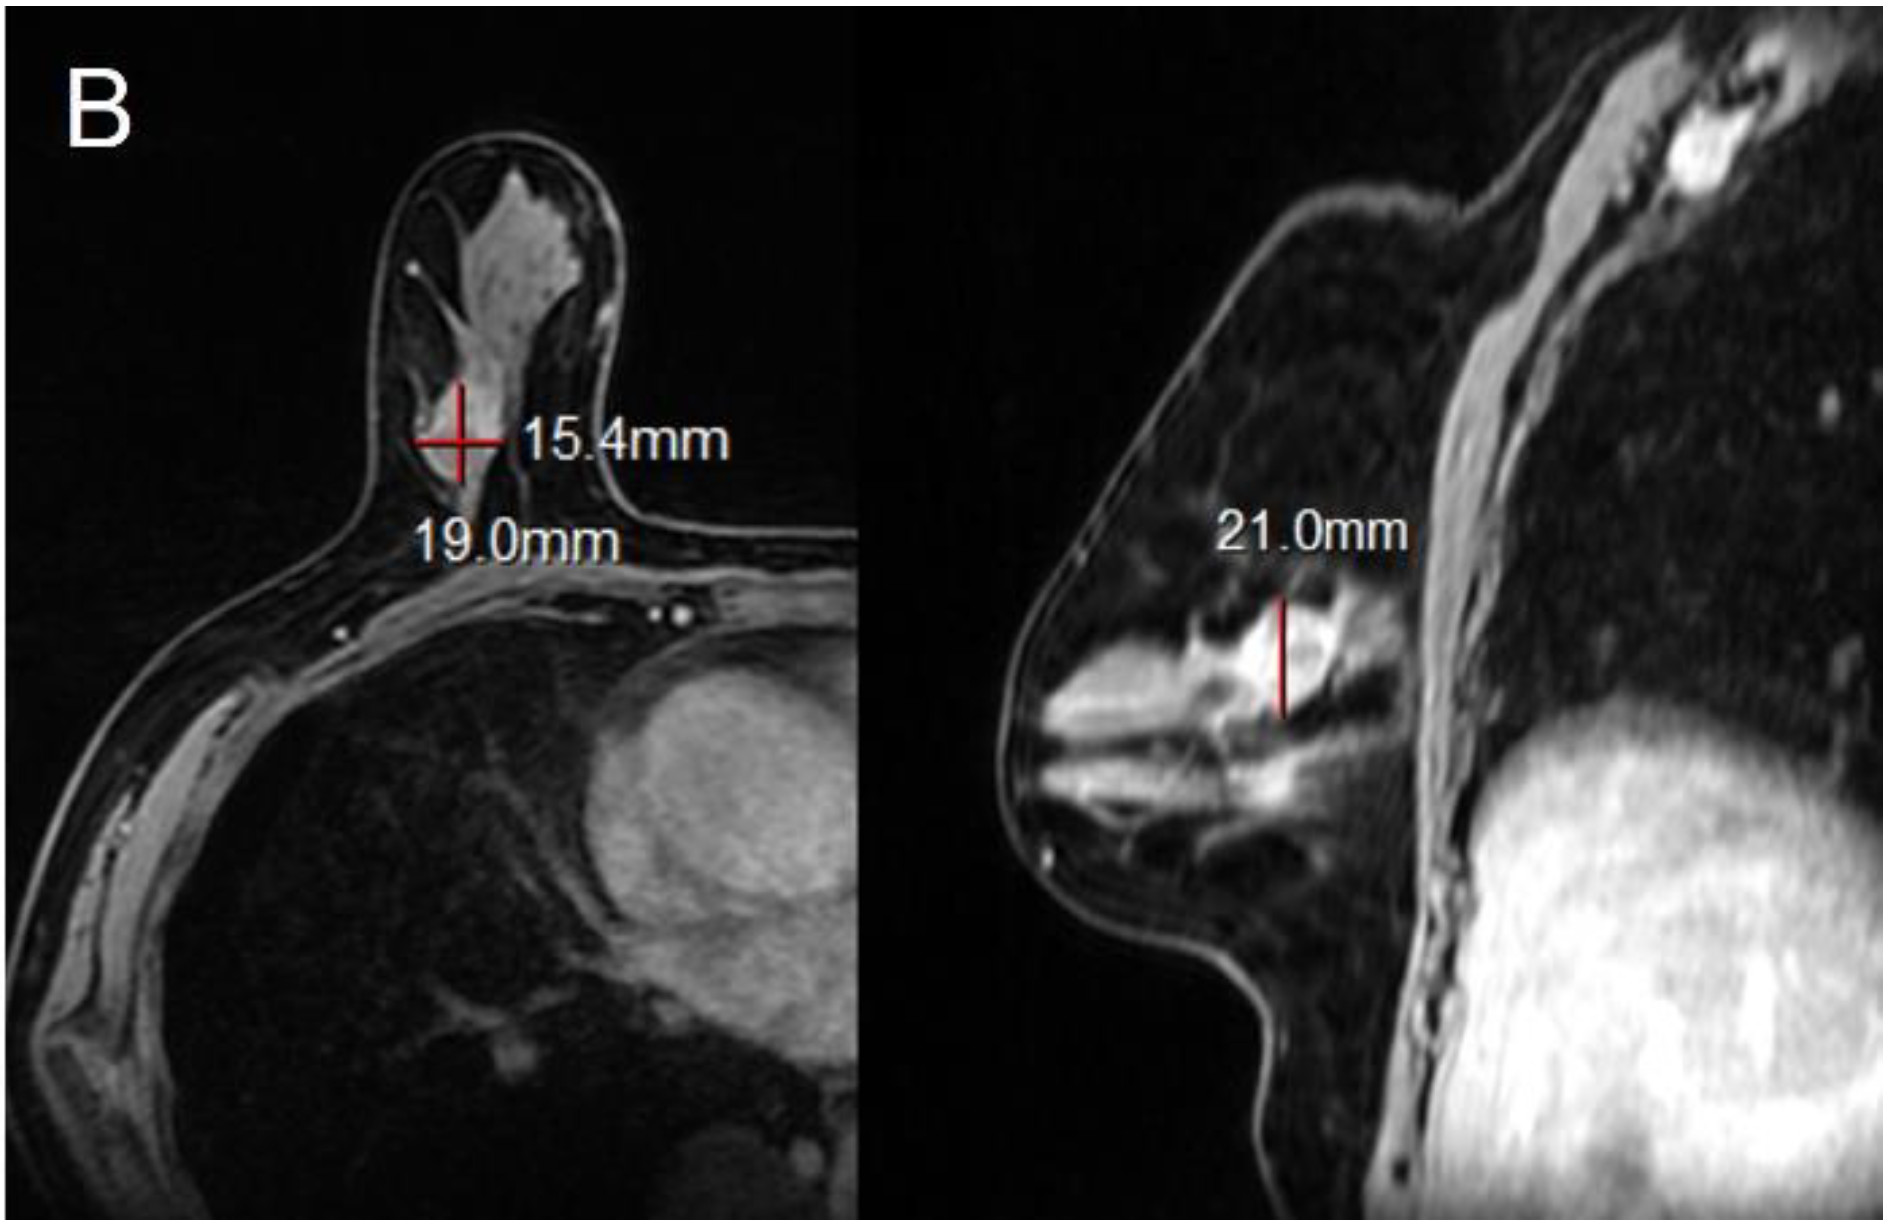

Figure 4.

42-year-old woman with ductal carcinoma in situ in left breast. (A,B) Maximal diameter by CAD, radiologist and pathology were 7.1 cm, 7.5 cm, and 5.5 cm. Both CAD-and radiologist-measured sizes were inaccurate, in reference to pathology. This cancer was of HER2+ subtype, positive EIC at pathology and non-mass enhancement type on MRI (L: left, LO: lower outer).